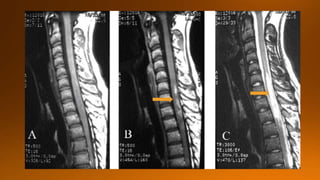

The images are of a child .The images are non-specific with multiple focal lesions and probably

the first choise would be MS.

The differential diagnosis would include inflammation, infection and metastases.

In such cases always perform a transverse image of the spine to look for the exact location and

perform a MRI of the brain.

The lesions are located dorsally and one of the lesions is enhancing.

Now if this was infection or metastases it would be strange that not all lesions enhance.

MS is still on our list.

We continue with brain images in next slide